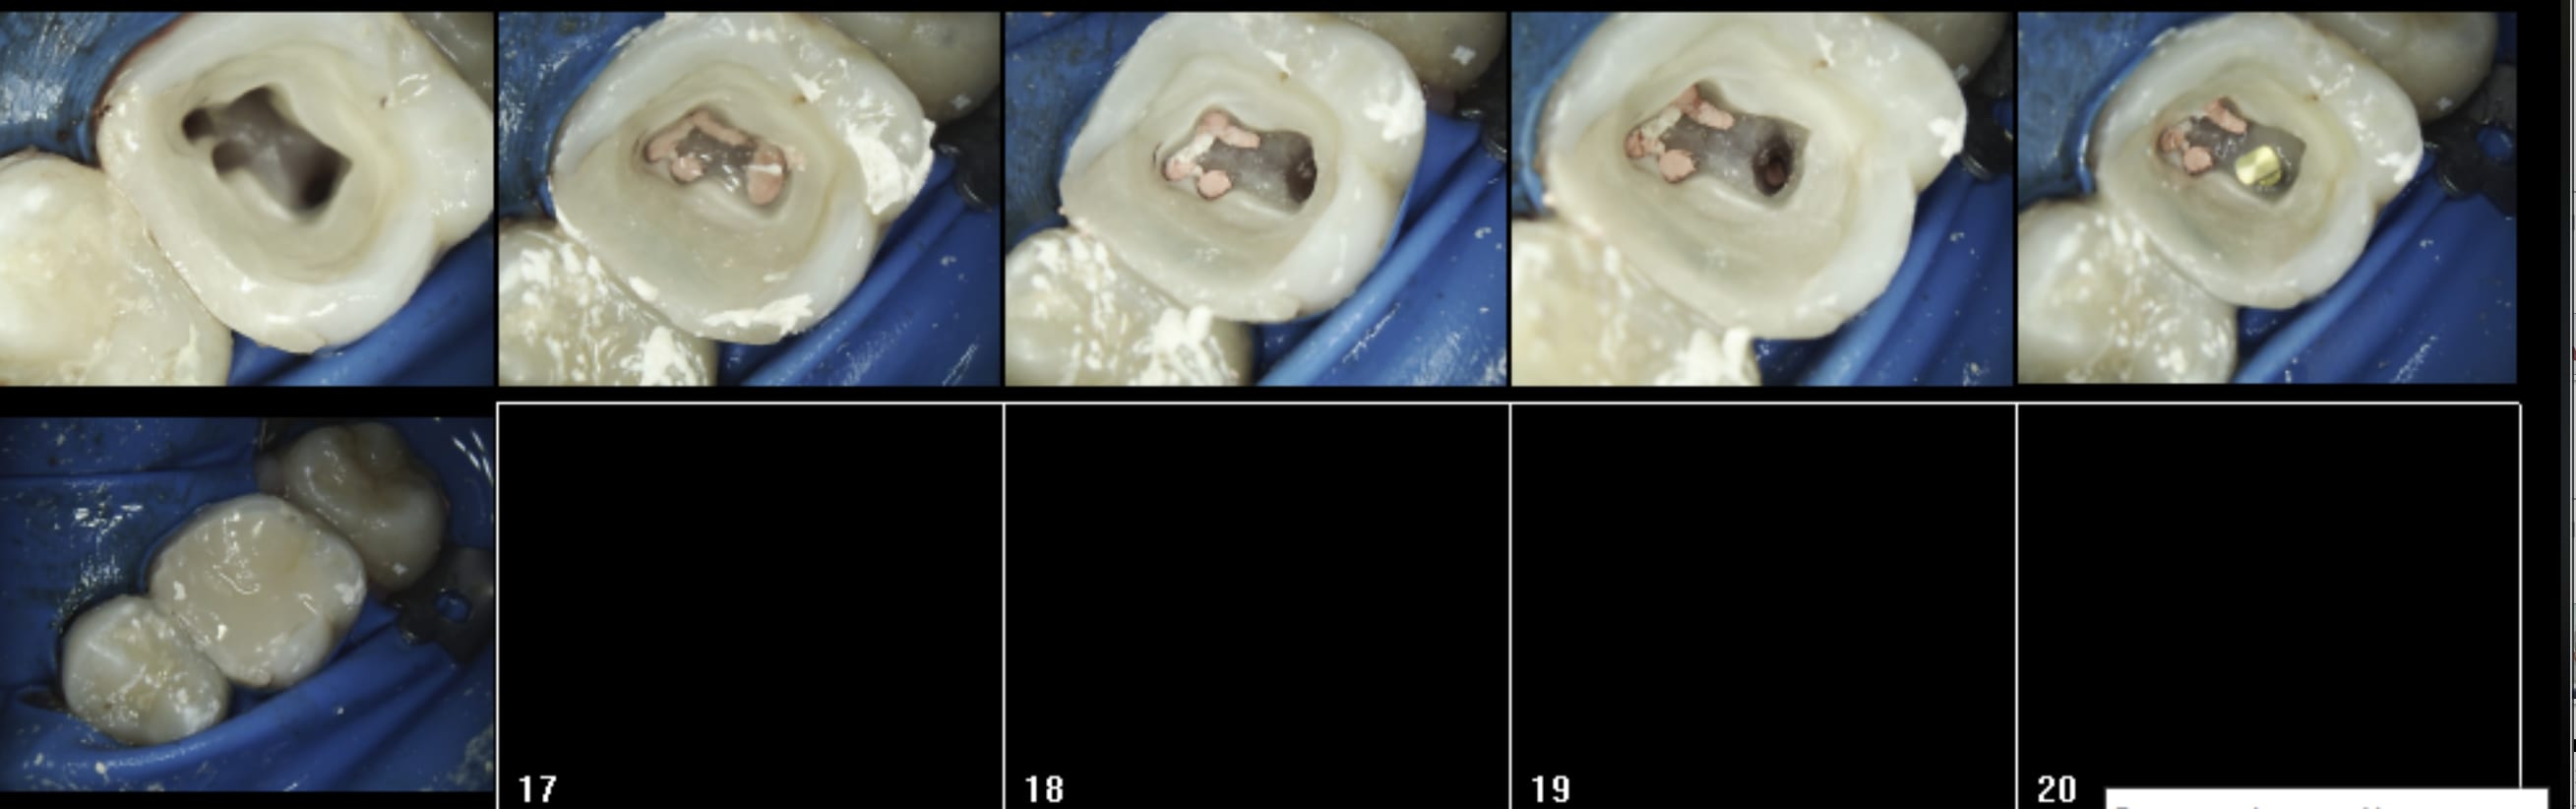

Je ne fais plus de radio MC en place depuis 5 ans

Uniquement localisateur d'apex + digue (pour que le localisateur ne merde pas) + radio pre op et radio post op

+ thermocompactage pour avoir une belle densité + restauration plastique avec/sans ancrage (95% du temps)

Le localisateur est infiniment plus precis qu'une radio MC qui n'est au final qu'une image 2D et n'indique qu'a +- 2mm ton apex

Oui ça fonctionne... mais la recommandation HAS c'est trois radios, pré, per, post, si tu as un problème un jour, avec deux radios tu es en défaut. Donc prenable.

Profs ou pas, tu fais un endo 36, pas de perop, gutta condensor et tu touches le nerf alvéolaire inférieur, c'est de ta faute, avec une per OP c'est un aléa.